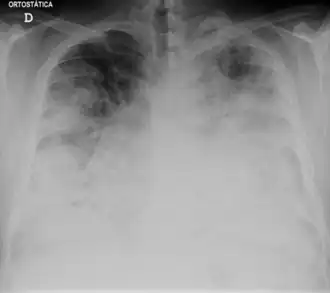

La radiographie du thorax peut montrer un infiltrat pulmonaire ainsi qu'un épanchement pleural. Les images peuvent persister un certain temps après la fin du traitement[26].